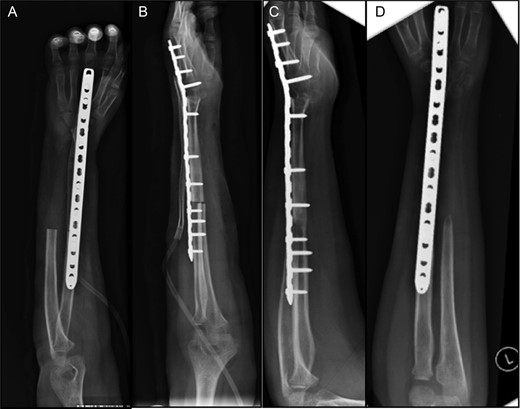

Upon removal of the mass, the distal halves of the right ulna and radius were resected. Dorsal plate fixation was used to stabilize the allograft, which extended from the native proximal radius to the proximal carpal row, effectively creating a single-bone forearm (Fig. 5).

(A and B) Post-operative radiographs of allo-arthrodesis with dorsal plate fixation. (C and D) Follow-up radiographs at 7 months post-op.

Post-operatively, the patient began occupational therapy 1 week after surgery, completing 13 sessions over several months, with a progressive increase in strength, range of motion and coordination of the left upper extremity. At 8 weeks, the patient was able to employ pincer grasp to pick up small marbles and make a fist at 10 lbs of force, with minimal pain on palpation as well as during therapy exercises. At the request of the patient's family, they were given a hand-strengthening routine to continue at home. At 12 months follow-up, the patient has exhibited excellent recovery, including normal range of motion at the shoulder and elbow and ability to perform all activities of daily livings despite reduced grip strength. On all follow-up imaging, the allograft has fully incorporated, with no hardware failure or loosening.